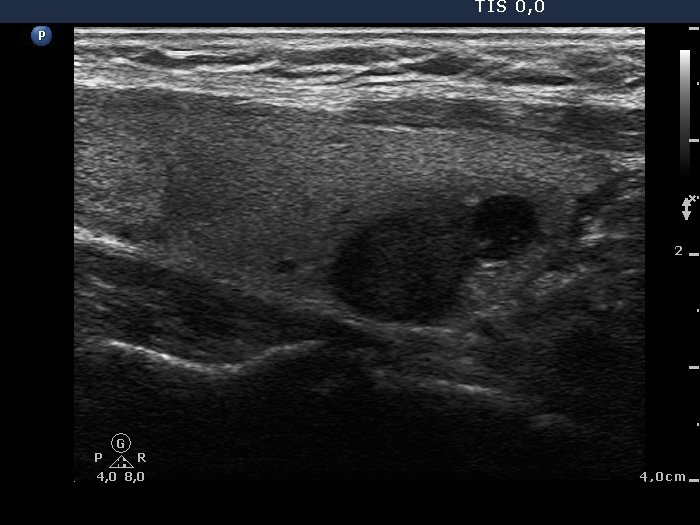

Third row: 19 months after sclerotherapy. The dimensions of the nodule were 15x14x19 mm (width x depth x length).